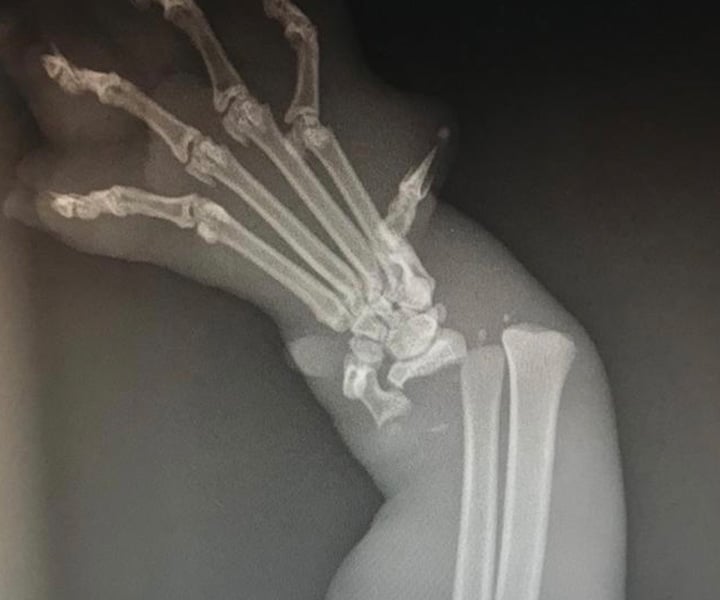

The team noticed he had a very swollen foot and after an X-ray, they could see his foot was severely broken, and looked like it had been for at least a couple weeks to a month as there was an infection on the skin and throughout the bone. The cat, who was given the name Beetle, was immediately given pain relief to prevent further suffering and make him as comfortable as possible.

Due to the infection, amputation was unfortunately little Beetle’s best option. Student Nurse, Millie, prepped Beetle for his big surgery and Lead Vet, Silvia, performed the surgery. Following his amputation, Beetle has been recovering well and has taken to life on three legs brilliantly.